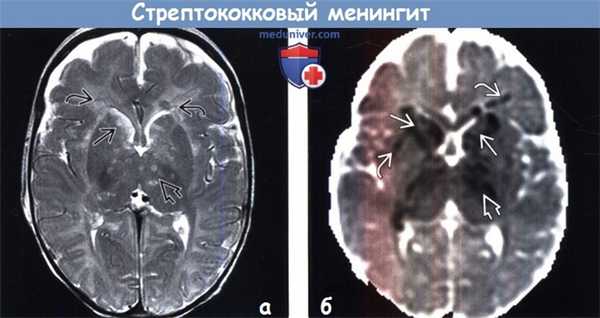

(а) МРТ, Т2-ВИ, аксиальный срез: определяются гиперинтенсивные очаги в базальных ганглиях, таламусе и белом веществе, которые представляют собой очаги инфарктов, развившихся вследствие воспаления в периваскулярных пространствах/артериита.

(б) МРТ, ИКД, аксиальный срез: у этого же пациента определяются множественные инфаркты в базальных ганглиях и таламусе. Обратите внимание на рассеянные участки инфарктов в белом веществе. Лучшим методом выявления инфаркта в раннем периоде является диффузионно-взвешенное изображение, поскольку в данные сроки на Т2-ВИ и FLAIR-изображениях изменений может не наблюдаться.